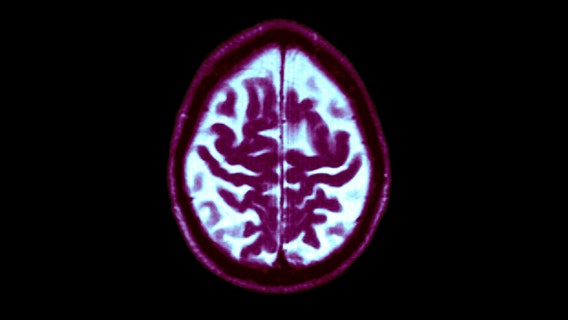

Study: Middle-aged people who sleep less than than 7 hours nightly may have increased risk of dementia

A recent study highlighted by the National Institutes of Health found that middle-aged people who slept less than seven hours a night and/or had irregular sleep patterns could be at higher risk of developing dementia later in life.